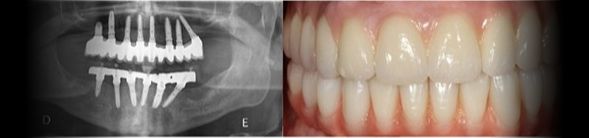

Caso clínico sobre Implantes Dentários